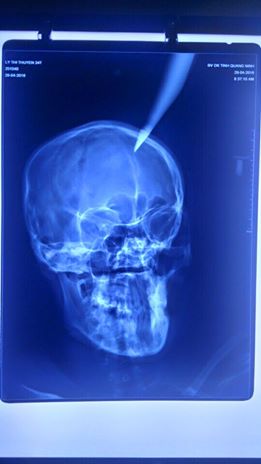

Thai phụ được đưa đến bệnh viện với con dao nhọn cắm sâu 4 cm vào đỉnh đầu

Bệnh nhân L.T.T. (24 tuổi, trú tại xã Nam Sơn, huyện Ba Chẽ, tỉnh Quảng Ninh) được chuyển từ bệnh viện địa phương đến Bệnh viện Đa khoa tỉnh Quảng Ninh vào chiều ngày 29-4 trong tình trạng nguy kịch với con dao nhọn dài khoảng 20 cm đâm giữa đỉnh đầu. Nạn nhân đang mang thai ở tháng thứ 5.

Kết quả chụp X-quang cho thấy phần đầu nhọn của dao cắm sâu 4 cm vào não. Theo người nhà bệnh nhân, vụ tai nạn hi hữu xảy ra khi bố chồng của chị T. sửa mái nhà đã vô tình làm rơi con dao dắt trong người xuống, cắm thẳng vào đầu con dâu đang đi qua ở phía dưới.